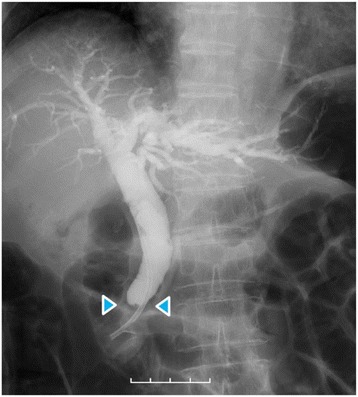

Dynamic computed tomography (CT) showed bile duct wall thickening that was enhanced in the lower part of the CBD (Fig. 2). Endoscopic retrograde cholangiography (ERC) demonstrated abrupt obstruction of the lower CBD (Fig. 3). Histological examination of biopsy specimens from the lower CBD showed adenocarcinoma with signet-ring cells. We diagnosed extrahepatic cholangiocarcinoma and performed subtotal stomach-preserving pancreaticoduodenectomy (SSPPD). The surgery lasted 348 min, and the total blood loss was 525 mL. Histopathology report suggested atypical epithelial cells exhibiting infiltrative growth, with fibrosis of the duodenal papilla (Fig. 4c). Tumor cells displayed intracytoplasmic mucus deposition, crescent-shaped nucleoli (Fig. 4d, e) extensions along the lower CBD, and invasion of pancreatic parenchyma (3 mm). AcbBd, exposed protruded type, 22 × 16 mm, por2/sig, pT3a, sci, INFc, ly1, v1, ne1, pN0, pHM0, pPM0, pEM0, PV0, A0, R0, pStage IIA according to the Japanese Classification on Cancer of the biliary tract [ref. 2] and pT3N0M0 stage IIA in accordance with Union for Internationatinal Cancer Control, 7th edition. The final diagnosis was poorly differentiated adenocarcinoma with signet-ring cell of DPC. The patient developed pancreatic fistula postoperatively (ISGPF grade B), with no other complications and was discharged on day 37 postsurgery. She has remained disease-free for 5 years since the surgery.